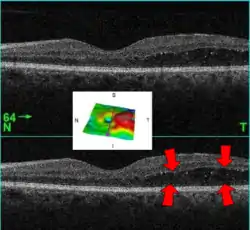

![]() رجل في السادسة والستين من العمر يعاني من مرض السكري من النوع الثاني ,وتمثل هذه الصورة وذمة بقعية,تم تصويرها باستخدام جهاز التصوير الطبقي للتماسك البصري(الأسهم تشيرالى الوذمة).الصورة الموجودة في الوسط عبارة عن تمثيل ثلاثي الأبعاد سمك شبكية العين(الوذمة ملونة باللون الاحمر).). رجل في السادسة والستين من العمر يعاني من مرض السكري من النوع الثاني ,وتمثل هذه الصورة وذمة بقعية,تم تصويرها باستخدام جهاز التصوير الطبقي للتماسك البصري(الأسهم تشيرالى الوذمة).الصورة الموجودة في الوسط عبارة عن تمثيل ثلاثي الأبعاد سمك شبكية العين(الوذمة ملونة باللون الاحمر).). | |